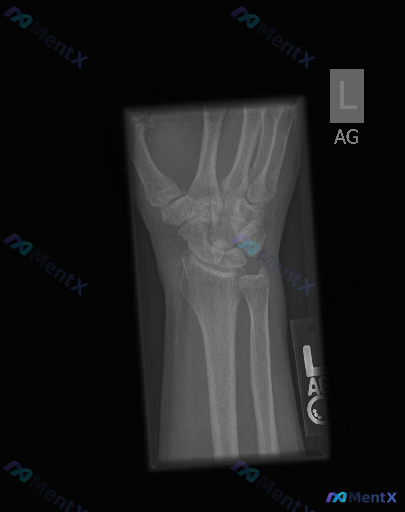

左侧手腕正位X线片未见明确骨折,但临床提示存在异常,你会优先考虑什么?

整理到一份左侧手腕正位X光片的评估资料,想和大家讨论一下这类“看似正常但需明确异常方向”的情况。 病例影像评估(常规视角) - 骨结构与完整性:桡骨远端、尺骨远端、8块腕骨形态大致正常,皮质连续,未见明确骨折线;腕骨排列有序,无明显脱位/移位。 - 关节间隙与对位:桡腕关节、下尺桡关节、腕中关节间隙...